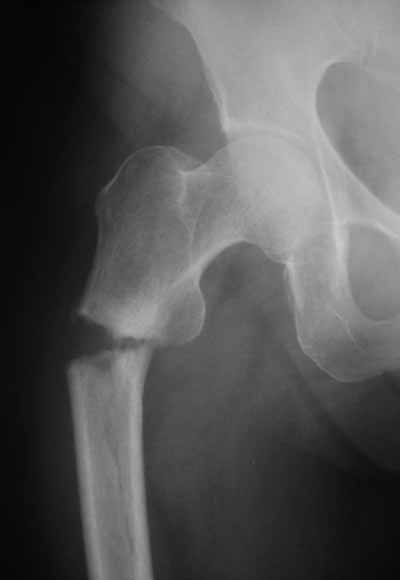

Да? Качество рентгенограмм конечно неочень, но ведь это нестабильный перелом 31.А2.2, не так ли?

Не думаю так. см вложение.

> Не думаю так. см вложение.

Для такого перелома вполне может быть использован диафизарный штифт, который отечественного производства я даже боюсь считать во сколько раз дешевле... Недавно несколько примеров я закидывал.